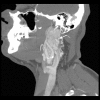

Material/methods: A total of 72 patients with SDHx mutations underwent computed tomography examinations of the head and neck. HNP were present in 44 (61.1%) out of 72 patients (31 SDHD, 11 SDHB, 2 SDHC); 113 HNP were found; the most common were carotid paragangliomas (59) and vagal paragangliomas (27).

Results: The HNP were statistically more frequent in carriers of SDHD mutations compared to carriers of SDHB mutations (72.1% vs. 43.5%, p=0.033). Multiple tumors more often occurred in patients with SDHD mutations 26/31 (83.9%) than in patients with SDHB mutations 6/11 (54.5%) p=0.05. There was a significant difference in the prevalence of carotid paragangliomas between patients with SDHB and SDHD mutations (7/11 [63.6%] vs. 30/31 [96.8%], respectively, p=0.004). Patients with SDHD mutations more often had carotid paragangliomas located on the left side than on the right side, as compared to SDHB mutations 25/31 (80.6%) vs. 4/11 (36.4%), p=0.006.

Conclusions: SDHx mutations predispose to multifocal and bilateral HNP. Carotid and vagal paragangliomas occurred most often. Patients with SDHD mutations are characterized by higher frequency of HNP than patients with SDHB mutations, which is mainly driven by higher frequency of carotid body tumors in patients with SDHD mutations. No difference in the frequency of head and neck paragangliomas in other locations was found.